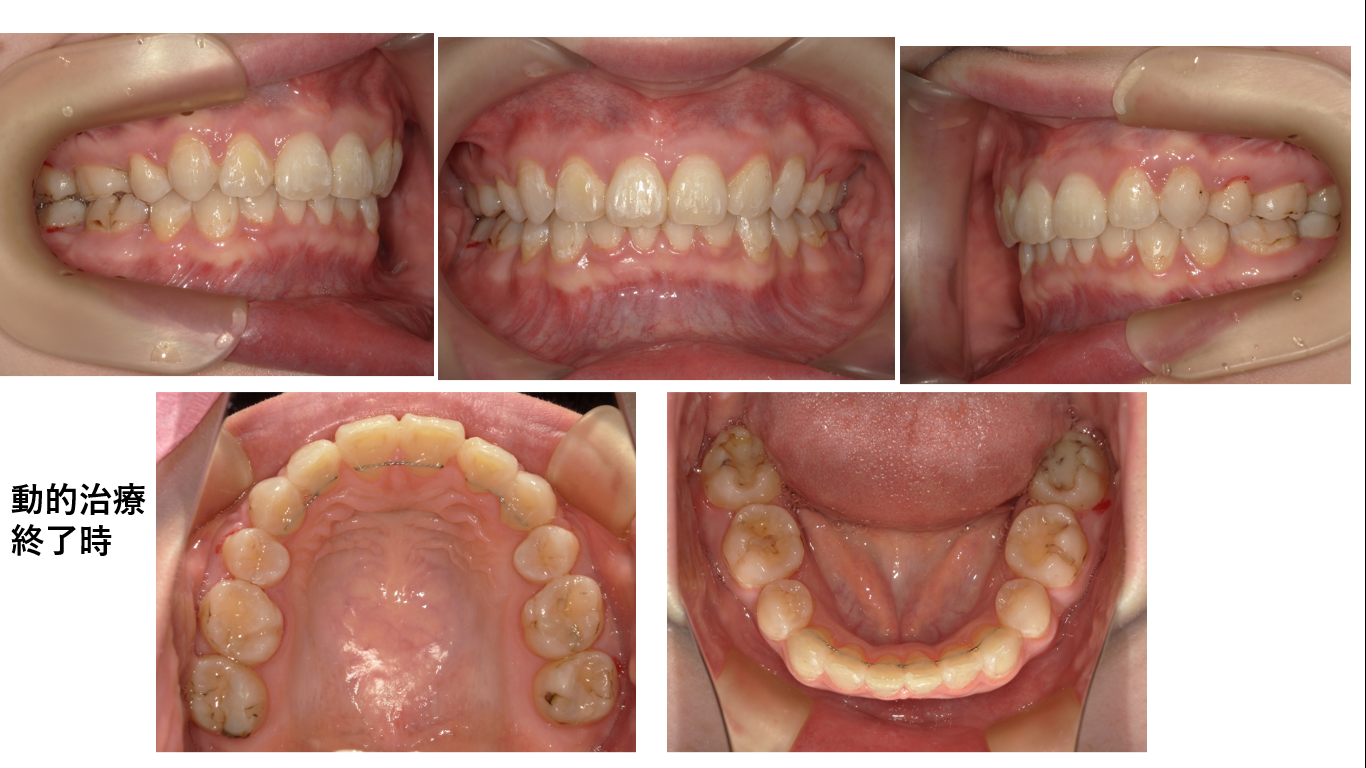

矯正症例144 AngleⅡ級2類

初診時32歳 抜歯部位上下左右4番、8番、治療期間2年8か月、治療費総額1,120,000(税込み)

装置を外した後は『自分じゃないみたい!』と喜んで下さりました。何はともあれ喜んでもらえて良かったです。